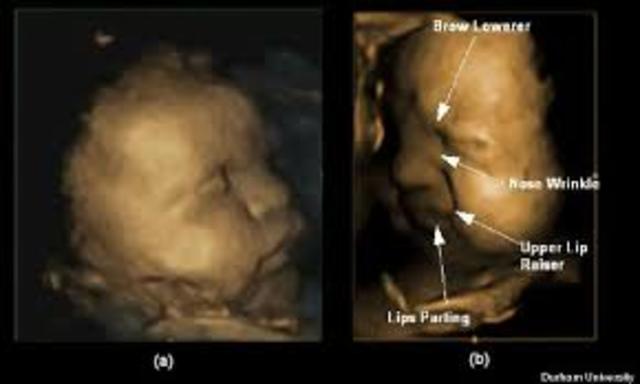

The nostrils, mouth, lips, and eyelids form. Second, the fingers and toes are almost complete. The fetus is about an inch long.

The fetus weighs about 1 ounce. The fetus can also suck it's thumb, and the facial structure becomes more clear. The fetus is aobut 3 inches long.